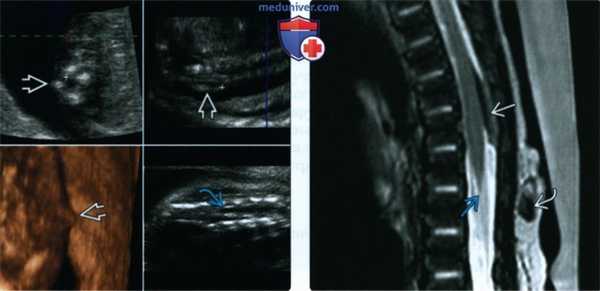

(Слева) Т1-ВИ, сагиттальная проекция (клиника СФСМ): аномально удлиненный спинной мозг, продолжающийся по меньшей мере до уровня L5 и незаметно переходящий в утолщенную терминальную нить, которая прикрепляется к небольшой терминальной липоме. Признаки сочетанной сирингогидромиелии отсутствуют.

(Справа) Т2-ВИ, аксиальная проекция (клиника СФСМ): низкорасположенный, но нормальный во всех остальных отношениях спинной мозг, оканчивающийся на нижнепоясничном уровне. (Слева) Продольный УЗ-скан (новорожденный с подозрением на фиксированный спинной мозг) с признаками низкого расположения и гидромиелии спинного мозга, продолжающегося до уровня S1. Данные сонографии свидетельствует о том, что полость в спинном мозге является продолжением его центрального канала.

(Справа) Это сагиттальное Т1-ВИ (новорожденный с подозрением на фиксированный спинной мозг) подтверждает картину аномального низкого расположения спинного мозга, характеризующегося наличием сирингогидромиелии и короткой утолщенной терминальной нити, прикрепляющейся к терминальной липоме в дистальном отделе дурального мешка. (Слева) На сагиттальном Т2-ВИ (аномалии позвоночника, клиника СФСМ) определяются признаки врожденной аномалии сегментации L1-L4 позвонков, являющейся причиной фокального кифоза поясничного отдела позвоночника. Спинной мозг оканчивается на уровне L1-L2, однако аномально заострен и фиксирован утолщенной и как будто натянутой терминальной нитью.

(Справа) Это аксиальное Т1 -ВИ (аномалии сегментации позвоночника, клиника СФСМ) подтверждает наличие жировой инфильтрации терминальной нити, которая кроме того характеризуется аномальным расположением в центральной части дурального мешка.